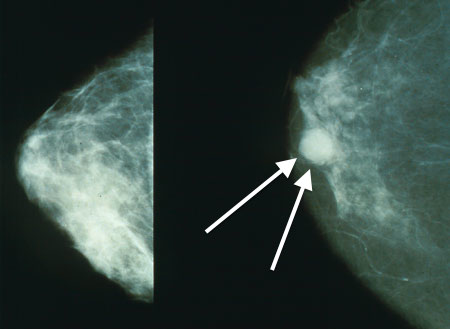

1. Protuberâncias

Os nódulos são indicadores primários de que há algo irregular em seus seios. Eles não precisam ser doloridos ou causar desconforto para serem cancerosos. Além de sua presença nos seios, eles também podem ocorrer nas axilas.